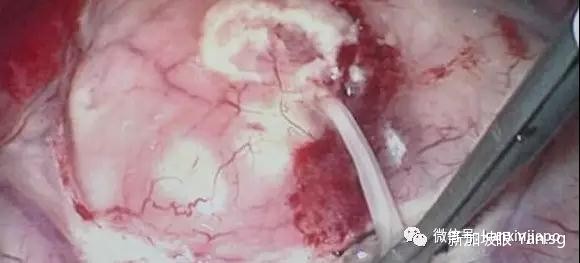

重者,虫卵或幼虫会进入血液,随后进入大脑,并在大脑停留、繁殖。抽搐、昏厥、癫痫等症状也是常有发生。

(脑中取出的曼式裂头蚴虫)